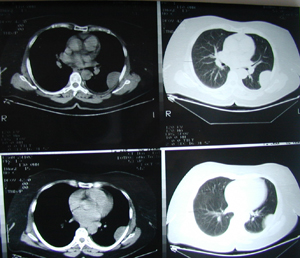

Εικόνα 3α-δ

Αξονική τομογραφία θώρακος σε διαφορετικά επίπεδα. Μάζα μαλακών μορίων που καταλαμβάνει το μεγαλύτερο μέρος του άνω λοβού. Η μάζα πιέζει την πνευμονική αρτηρία, τον κύριο βρόγχο και την άνω κοίλη φλέβα και πρόκειται για μάζα εκ μαλακών μορίων με νεκρώσεις κατά περιοχές.

Α-Β

Γ-Δ